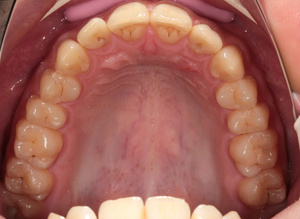

Для устранения разночтений в плане лечения в клиниках сейчас широко внедряется дентальная макрофотография, которая помогает врачу и пациенту объективно определить необходимость лечения или отсутствие последней. Разногласий с пациентами возникает гораздо меньше.

Инрооральные камеры начал применять одним из первых в Новосибирске.Итрооралкой фиксируется каждый этап лечения(акт скрытых работ). Но она не дает полномасштабной качественной картинки. Со временем, пришёл к выводу, что это дешевое дополнение к другим оптическим дивайсам.